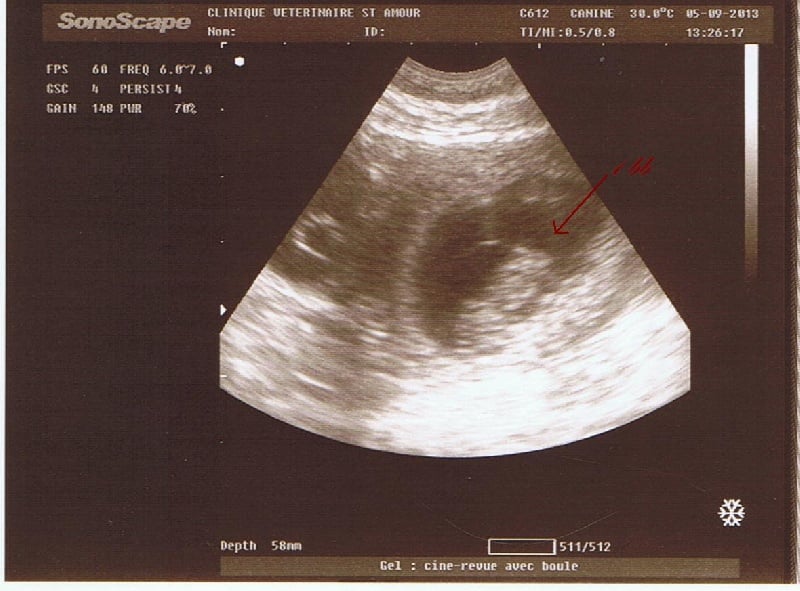

Et bien voilà, après un mois de patience, nous avons fait l'échographie de gestation de notre pépette. Nous espérions qu'elle soit positive car la belle avait légèrement grossi, et coté appétit, bien que Paprika soit un glouton habituellement, là on va dire que c'était ++++. Donc 14h chez le véto, mise en place de l'appareil, tonte du bedon de madame, et là recherche d'ampoules foetales !!!!! une question est posée par le véto "elle a fait pipi avant de venir ??," " euh, et bien oui, comme à toutes ses sorties ;-)" donc recherche, et hop !! une ampoule, un petit coeur qui bat, mon dieu, je suis émerveillée à chaque fois, quel bonheur de voir ce petit bb bouger. Et quelle joie pour nous que la belle soit gestante. Donc maintenant croisons les doigts pour que tout ce passe bien pour le mois restant, et normalement naissance des petits nounours autour du 06 octobre. Encore de la patience !!! Ci dessous la photo de l'échographie.